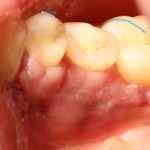

Вот фотография послеоперационной раны через пару дней:

Так, друзья, выглядит нормальная послеоперационная рана. Со швами я угадал. Это, кстати, Prolene 5-0.

А вот фотография через месяц после операции:

Задайтесь вопросом — оно того стоило? 30 минут в операционной, 4 дня на реабилитацию и 2 недели со швами? Стоило ли это того, чтобы в будущем избежать серьезных проблем со здоровьем?